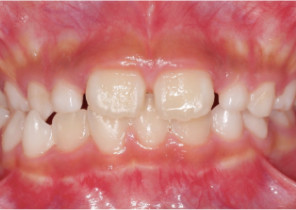

Case Report 2

7 years 11 months old, 24 stages of Invisalign® Palatal Expanders

Courtesy of Dr. David R. Boschken

Pre Invisalign Palatal Expander Expansion

Post Invisalign Palatal Expander Expansion

Post Invisalign Palatal Expander Treatment